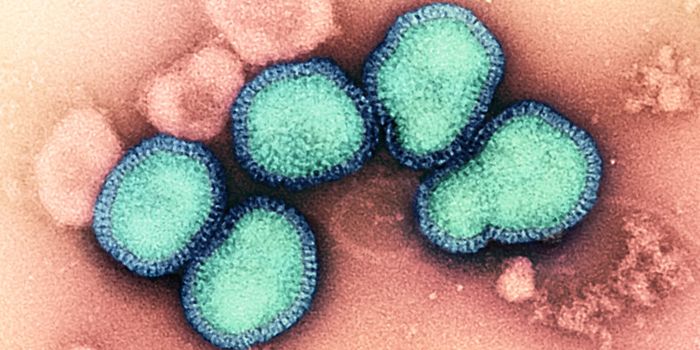

JUN 21, 2024Clinical & Molecular DXThe overwhelming majority of people that think they have the flu never get tested, even when they see a doctor about it, ...

APR 09, 2024Genetics & GenomicsDuring the 2009 H1N1 influenza pandemic, there was a marked increase in neurological complications such as febrile seizu ...

DEC 20, 2023MicrobiologyA new SARS-CoV-2 subvariant of interest called JN.1 has been identified by the World Health Organization (WHO). Multiple ...

SEP 05, 2023Cell & Molecular BiologyIn recent years, a strain of highly pathogenic avian influenza, H5N1, has been devastating bird populations around the w ...

MAY 31, 2023Genetics & GenomicsEven as the world grapples with COVID-19, there has been another massive outbreak of a viral pathogen called H5N1 influe ...